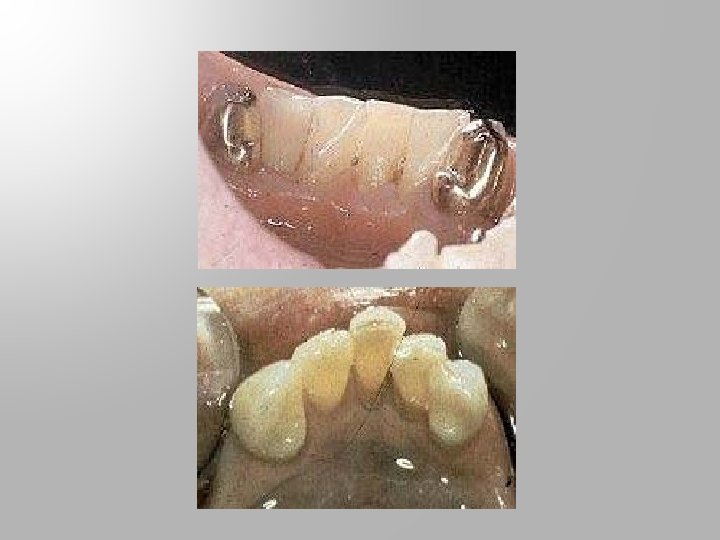

Guiding planes on abutment teeth supporting distal extension base

Guiding planes prepared on the lingual surface of abutment teeth

Reduction of a lingual bulge to eliminate obstruction areas and provide reciprocation.